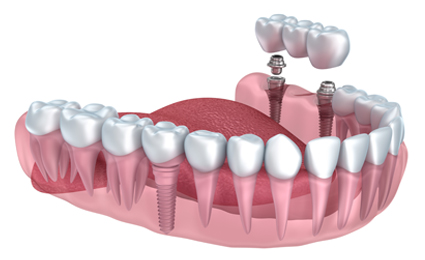

전체 임플란트

8개 이상의 임플란트를 수술하는 큰 수술이며, 환자의 구강구조를 정확히 파악해야 하기에 숙련도 높은 전문가의 식립이 필요합니다.

빠르고 체계적인 임플란트

우리에게 올바른 길을 알려주는 네비게이션처럼

디지털 기술을 통해 최적의 수술 경로를 알려주는

디지털 분석 임플란트.

3D 모의 수술을 통해 식립 위치를 정밀하게 파악하고

오차 가능성을 줄인 체계적인 임플란트 입니다.